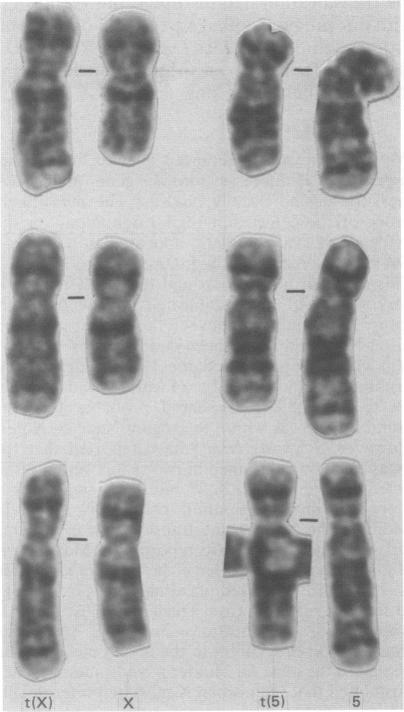

Cytogenetic re-evaluation of a fibroblast cell line from a female Hunter's syndrome case with a balanced X;autosome translocation, which had previously been reported to have a breakpoint in Xq26 to Xq27, showed the breakpoint to be either between Xq27 and Xq28 or within Xq28. The normal X chromosome was preferentially inactivated, supporting the view that the translocation had disrupted the Hunter gene. The new localisation is now in full agreement with our previous linkage work and other published data. Results of further linkage studies using probes defining the loci DXS86, DXS144, DXS100, DXS102, DXS105, F8C, and DXS134 are also consistent with our original conclusion that the Hunter locus lies within the distal region of the X chromosome long arm.

对一名患有平衡型X;常染色体易位的女性亨特综合征病例的成纤维细胞系进行细胞遗传学重新评估,该病例先前报道在Xq26至Xq27有一个断点,结果显示断点位于Xq27和Xq28之间或Xq28内。正常的X染色体优先失活,支持了易位破坏了亨特基因的观点。新的定位现在与我们之前的连锁研究和其他已发表的数据完全一致。使用定义DXS86、DXS144、DXS100、DXS102、DXS105、F8C和DXS134位点的探针进行的进一步连锁研究结果也与我们最初的结论一致,即亨特基因座位于X染色体长臂的远端区域。